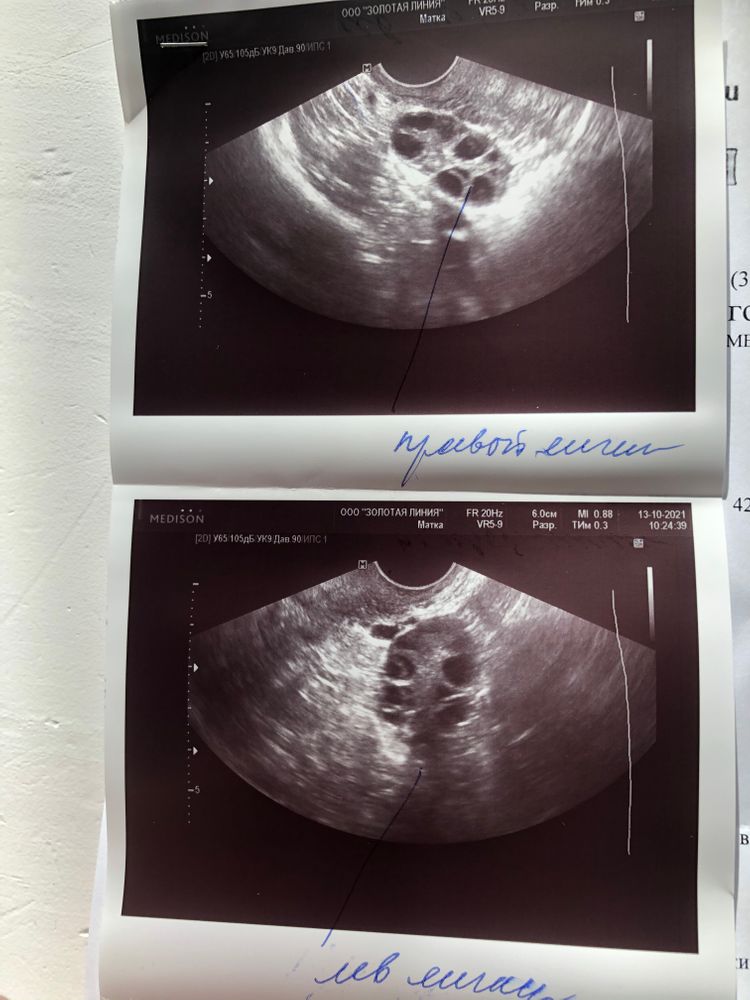

УЗИ ановуляторный цикл

Ановуляторный цикл!

И судя по картине, в которой столько фолликулов расположенные преимущественно по периферии, у меня часто бывают ановуляторные циклы😢😢😢 и нужна поддержка!